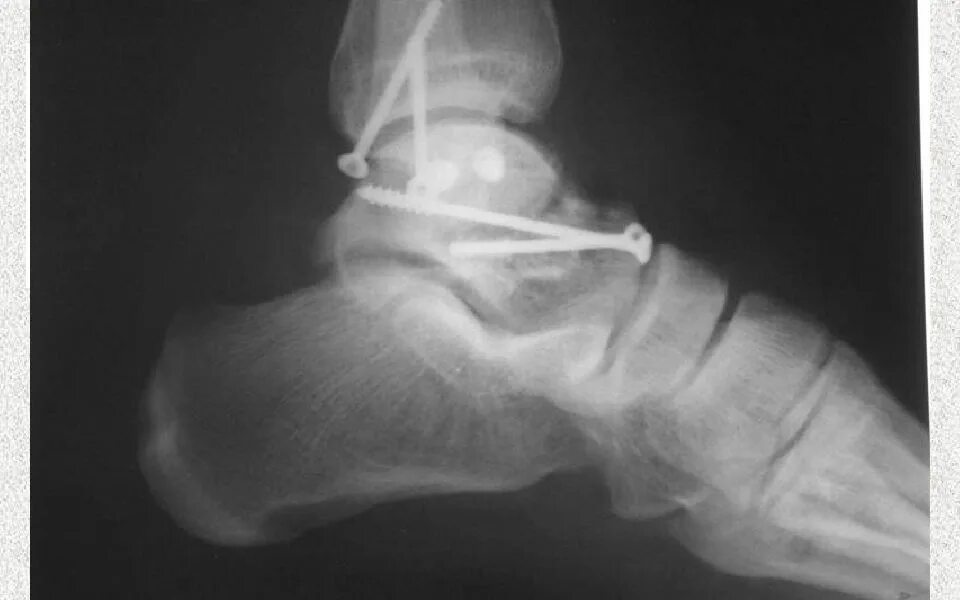

Перелом заднего